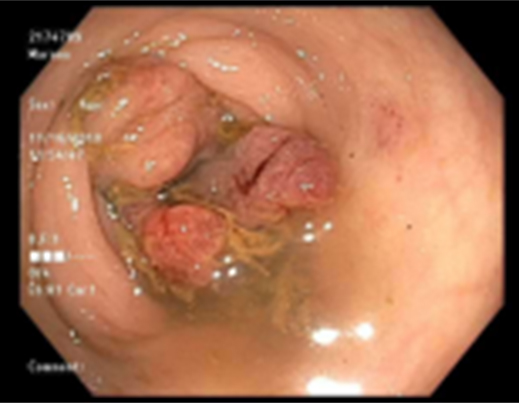

The patient then returned complaining of recurring abdominal pain. A second CT scan showed the abscess recurred in similar location to the primary (Figure 2). Since the second abscess was in the same location, the surgeon wanted a colonoscopy. The colonoscopy showed: “A severe stenosis measuring of unknown length was found in the descending colon (60 cm from anal verge) and was non-traversed. Biopsies were taken with cold forceps for histology. The exam was otherwise normal throughout the examined colon” (Figure 3), (Figure 4), (Figure 5). Biopsy performed showed highly atypical glands invading lamina propria, invasive adenocarcinoma.

Figure 3: Stricture seen during colonoscopy. “Findings: A severe stenosis measuring of unknown length was found in the descending colon (60 cm from anal verge) and was nontransversed. Biopsies were taken with a cold forceps for histology. Area was tattooed with an injection of spot (carbon black). The tattoo was placed on opposite walls approximately 3 cm below the stenosis. The exam was otherwise normal throughout the examined colon.”

Figure 4: Stricture seen in colonoscopy.

Figure 5: Descending colon in colonoscopy.